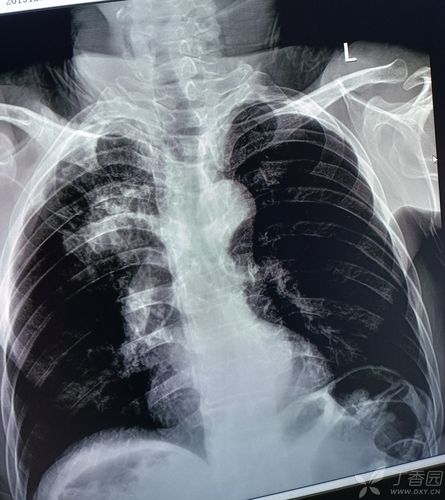

肺不张胸片典型图片

肺不张胸片典型图片,肺不张胸片表现图片

与肺不张,阻塞性肺炎并存时,可呈现反"s"形征象,有诊断意义.

左侧胸膜肥厚 b.左侧胸腔积液 c.左侧液气胸 d.左侧肺不张 e.

肺不张胸片表现图片

肺不张胸片表现

肺不张胸片

肺不张图片

肺不张x线表现图片

肺不张x线表现

肺不张x线